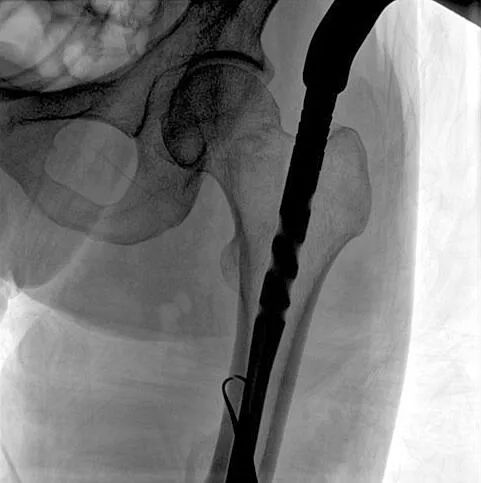

C形臂輔助手術(shù)過(guò)程

術(shù)中使用普愛(ài)醫(yī)療大平板一體式C形臂進(jìn)行透視,判斷骨折情況及克氏針、髓內(nèi)釘?shù)冉饘僦踩胛锏奈恢?,進(jìn)行調(diào)整。C形臂準(zhǔn)確的術(shù)中定位,大大縮短了手術(shù)的時(shí)間,減輕了患者的痛苦,輔助手術(shù)順利完成。

在進(jìn)行髓內(nèi)釘內(nèi)固定術(shù)時(shí),醫(yī)生需要同時(shí)觀察到入釘點(diǎn)和骨折部位的情況,普愛(ài)醫(yī)療大平板一體式C形臂采用30CM×30CM的平板探測(cè)器,能夠呈現(xiàn)更廣闊的成像面積,滿足大部分長(zhǎng)骨髓內(nèi)釘內(nèi)固定術(shù)的攝片需求。

術(shù)中定位準(zhǔn)確、出血量少,術(shù)后影像顯示股骨移位糾正,恢復(fù)良好力線,手術(shù)效果良好。